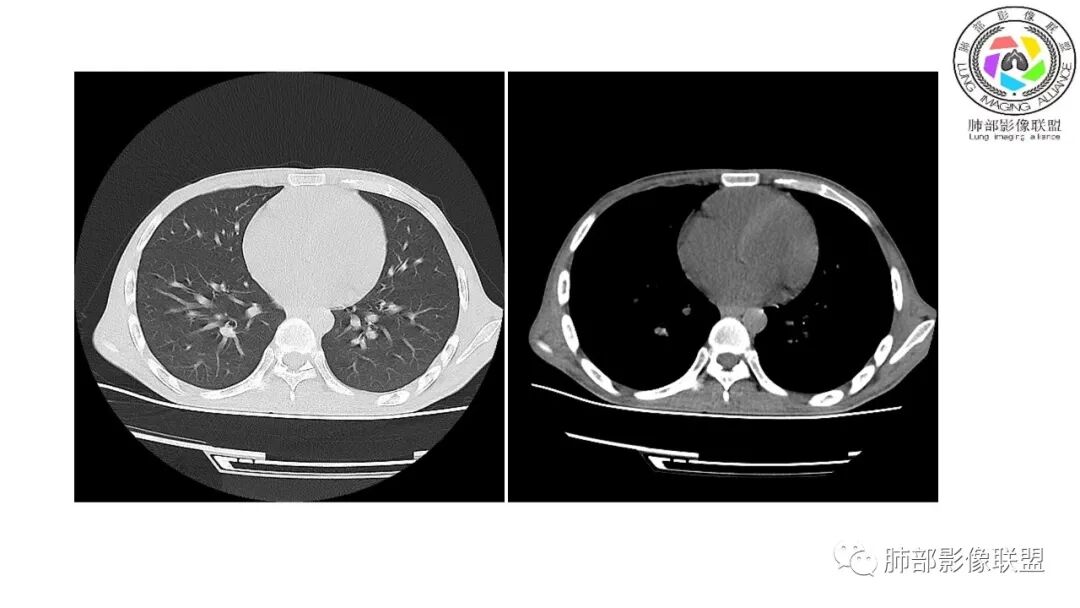

影像与临床:1.青年男性,HlV阳性,颜面部皮疹(未提供皮疹图像)、发热(高热),实验室CRP、PCT高,T-Spot阴性。2.右肺下叶空洞结节,壁厚不均,边界清楚,其内线状影,未见液平及钙化,未见卫星灶,纵隔淋巴结增大,双侧腋窝见增大淋巴结。心腔内低密度提示贫血可能。肝脾影增大,未见结节影及块影。腹膜后见多发增大淋巴结。

综合分析:本例肺部影像学改变并不具有特征性,空洞性病灶须与多种疾病鉴别,但年轻HIV阳性患者,高热,皮疹,肝脾增大,纵隔、腋窝、腹膜后见多发增大淋巴结等都强烈提示马尔尼菲篮状菌感染的可能性。